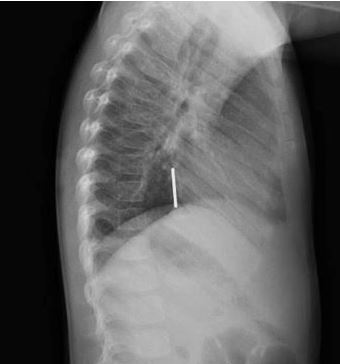

Answer: Esophageal Foreign Body (coin at level of GE junction)

- Coin in espophagus is en face on AP film vs. trachea en face on lateral film